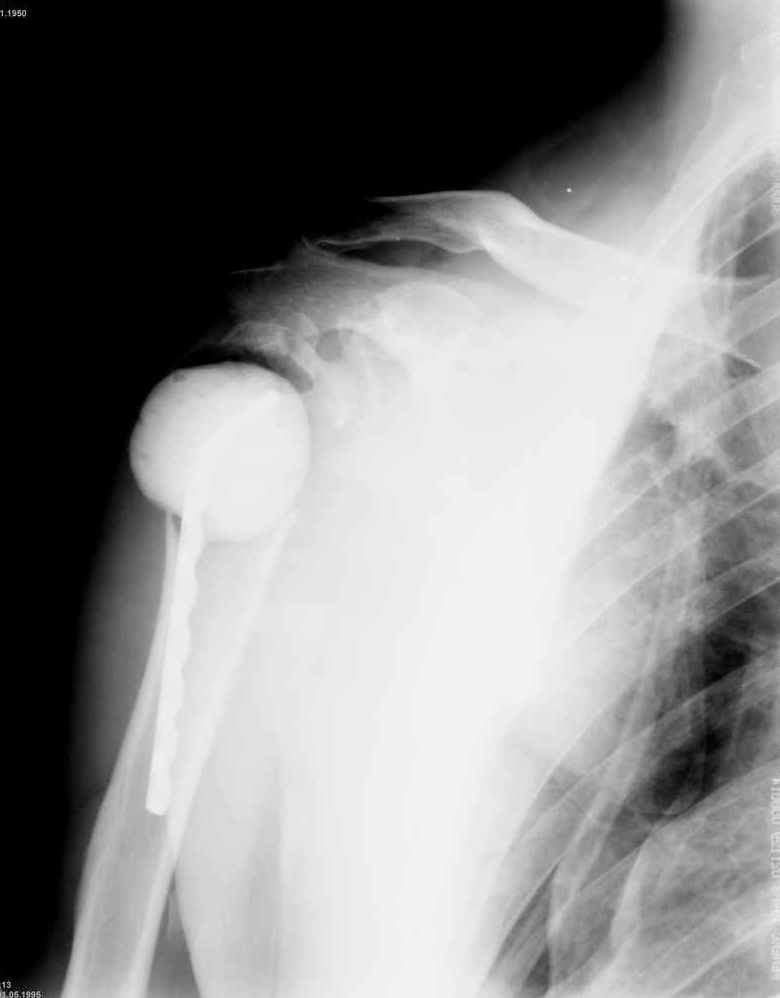

Уважаемые коллеги. Недавно из нашего отделения был выписан пациент 54 лет с закрытым переломом плечевой кости. Из анамнеза: за 2 дня до поступления в НИИСП, в состоянии алкогольного опьянения упал с лестницы на даче (высота 3-4 метра) с упором на правую руку. Через двое суток обратился за медицинской помощью. Доставлен бригадой "Скорой помощи".Правый плечевой сустав умеренно деформирован. По внутренней поверхности плеча имеется кровоподтек. При пальпации плечевого сустава имеется умеренная болезненность. Активные и пассивные движения болезненные. Снижена чувствительность по тыльной поверхности пальцев кисти и отсутствует активное разгибание кисти и пальцев. Имеется подкожная эмфизема шеи, верхней половины грудной клетки (рис 1, 2). На рентгенограмме: оскольчатый перелом головки плечевой кости со значительным смещением, перелом 2-3 ребер справа, тканевая эмфизема (рис 3). КТ при поступлении: перелом головки плечевой кости в области анатомической шейки со смещением отломка головки в грудную полость, правосторонний гидроторакс, перелом 2-3-4 ребер справа. (рис 4). Через двое суток после поступления выполнена операция: атипичная торакотомия, эвакуация свернувшегося гемоторакса, удаление инородного тела (головки плечевой кости) из плевральной полости (при этом выявлено имеющееся повреждение париетального и висцерального листков плевры) (рис. 5), дренирование плевральной полости, замещение проксимального конца плечевой кости спейсером из костного цемента с антибиотиком (рис. 6). Послеоперационный период протекал гладко. При контрольной рентгенографии положение спейсера удовлетворительное (рис. 7, 8). Дренаж из плевральной полости удален через 3 суток после вмешательства. Послеоперационная рана зажила первичным натяжением. Через 12 дней после операции больной выписан на амбулаторное лечение.